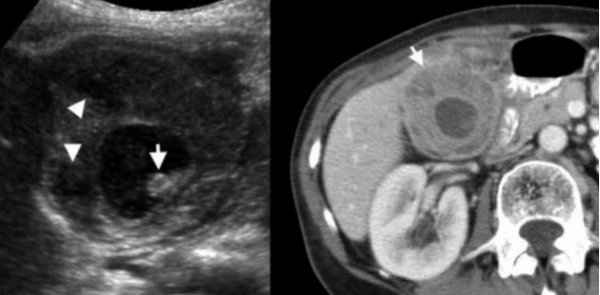

УЗИ и КТ желчного пузыря. Ксантогранулематозный холецистит. Слева на УЗИ визуализируется (помечено стрелками) утолщение стенки желчного пузыря с интрамуральным включением и с камнем в просвете органа. Справа на КТ выявляется утолщение стенки с гиподенсными включениями.

УЗИ (слева) и КТ (справа) желчного пузыря. На УЗИ ярко выраженное утолщение стенки желчного пузыря (указаны белыми стрелками). Множественные камни в просвете желчного пузыря (указано стрелкой). Компьютерная томография с контрастным усилением. На КТ визуализируются утолщение стенки с внутристеночными гиподенсными включениями. На КТ также выявлено, что процесс распространился на печень (указано стрелкой).